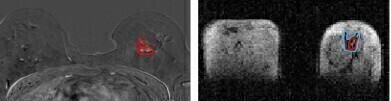

Side by side image of same breast tissue in MRI and FCI. (l) MRI image of breast with cancerous tumours circled in red (r) FCI image of same breast shows same tumour in red with secondary tumour spread in blue. Spread not visible in MRI. The patient had a mixed tumour i.e two different types of tumour and one of them is not visible in MRI. Photo Credit University of Aberdeen -

Photo Credit University of Aberdeen -